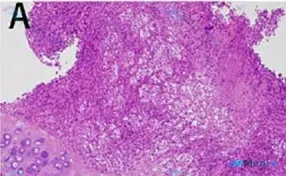

TBLB见非典型细胞+淋巴细胞浸润?别只想到肺癌/结核,这个软骨背景是关键线索

- 补充HE形态细节(结合读片):左下方可见残留的成熟软骨组织(软骨陷窝、同源群分布);右侧及上方为细胞密集区,结构紊乱,与正常软骨边界不清,呈侵袭性生长;高异型性细胞核深染、多形性、核浆比增高,部分可见核仁;间质有水肿/纤维化及炎症细胞浸润。

这个病例第一眼容易被“非典型细胞”带偏到肺癌,或被“淋巴细胞浸润”带偏到感染/结核,但那个“残留的成熟软骨”是个非常关键的锚点,不能轻易放过。

- 支持点:完美覆盖「成熟软骨残留(可能是被侵蚀的正常软骨或低级别成分)」+「高异型性、深染多形性细胞(去分化或高级别成分)」+「侵袭性生长模式」;

【当前最可能的收敛方向】

📋答案:结合现有HE形态学特征,高度疑似**软骨源性恶性肿瘤**(去分化软骨肉瘤或高级别软骨肉瘤,需优先排除转移性),其次需鉴别**淋巴瘤**及**肉芽肿性多血管炎(GPA)**等“假性浸润”病变。